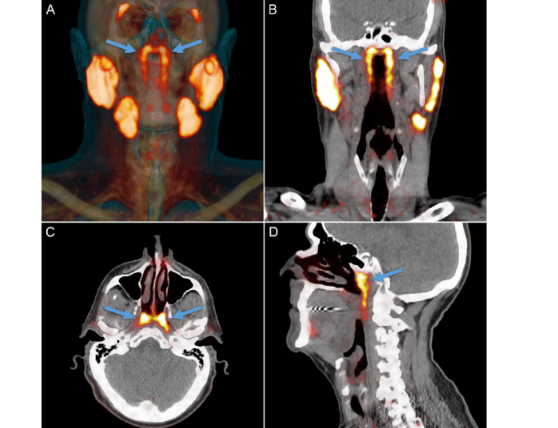

The researchers were using a specialized imaging method called PSMA PET/CT scanning. PSMA stands for Prostate-Specific Membrane Antigen — a molecule highly expressed in prostate cancer cells. These scans are commonly used in oncology to detect prostate cancer spread.

According to the National Cancer Institute, PET scans work by using radioactive tracers to highlight metabolically active tissue. In this case, PSMA tracers also bind to salivary gland tissue.

While scanning over 100 prostate cancer patients, researchers noticed consistent tracer uptake in the same region of the nasopharynx. That raised eyebrows.

To confirm their observations, the team examined cadavers and identified glandular tissue in that location. The findings were published in the peer-reviewed journal Radiotherapy and Oncology.